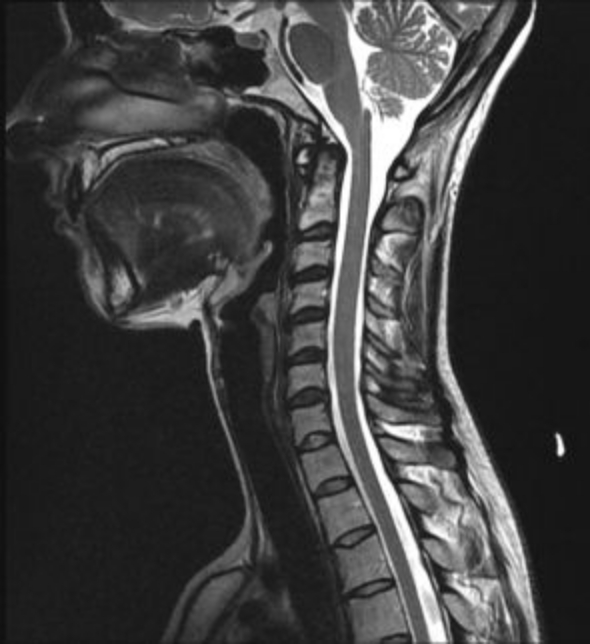

醫師能夠提供的服務,最重要的是診斷 : 頸椎狹窄的病因有許多,從發生率最高的椎間盤突出(俗稱骨刺)(圖2)、亞洲人(日本、韓國、台灣) 較常發生的後縱韌帶鈣化、到惡性腫瘤骨轉移(常見的攝護腺癌、肺癌、乳癌)(圖3)都有可能。從最基本的頸部X光到精密的核磁共振,醫師會依照症狀選擇合適的診斷工具。